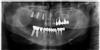

Wasja Опубликовано 29 декабря, 2012 Поделиться Опубликовано 29 декабря, 2012 Удаление оставшихся зубов в.ч.,одномоментная имплантация+ слепки для временных коронок Ссылка на комментарий